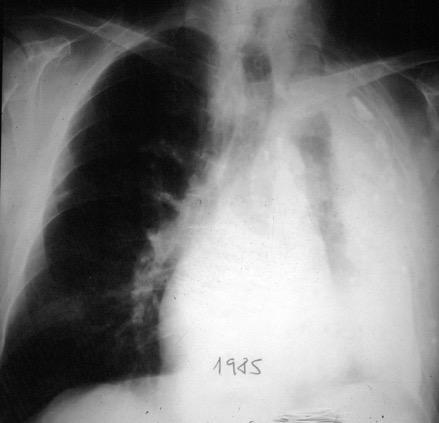

TB 25 años antes

Costillas “aumentadas de tamaño”

Causa más frecuente: Empiema crónico tuberculoso. Enfermedad pleural crónica y de larga duración

Tb con paquipleuritis calcificada, Hidroneumotórax. Cavidad apical conectada a pleura. Atelectasia redonda

Eyler WR et l. Rib enlargement in patients with chronic pleural disease . AJR 1996